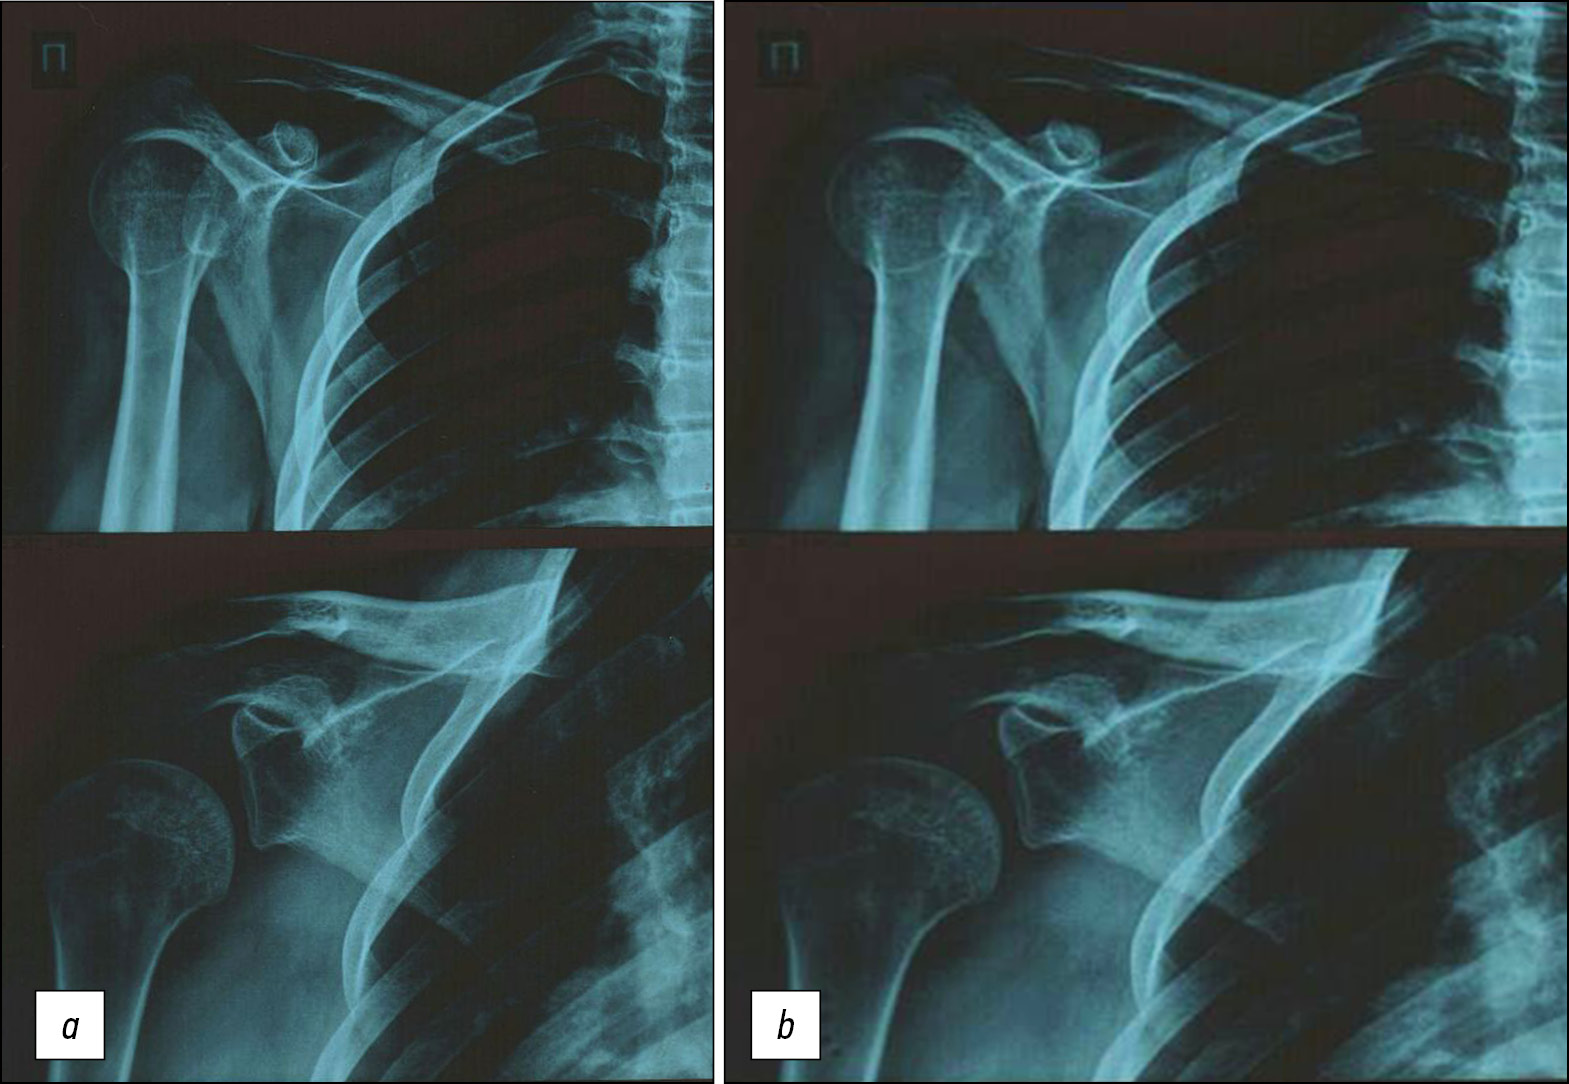

Shoulder joint bone structure examination (Fig. 1 a, b), as well as the identification of the signs of dysplasia, is advisable in patients with primary and recurrent instability to decide on a further management approach. The literature revealed a relationship between the counts of autoantibodies to certain types of collagen and the nature of external and cardiac manifestations of connective tissue dysplasia. An increased level of autoantibodies against types I and II collagens was registered in patients with pectus excavatum, scoliosis, severe joint hypermobility syndrome, and multiple intracardiac microanomalies. That to collagen type I was registered in cases of platypodia, and that to collagen types I, II, and V were revealed in patients with a prolapsing mitral valve myxomatous degeneration. An increased level of anti-collagen antibodies in patients with severe external and cardiac dysplastic signs indicates impaired autoimmune regulation mechanisms of collagen metabolism. The analysis of autoantibodies against collagen concentrations in the blood plasma of patients with joint hypermobility syndrome, considering its scoring [1], revealed high levels of autoantibodies of type I collagen with maximum values in severe articular hypermobility (4.9±0.5 and 6.2±0.7 µg/ml for mild and severe syndromes, respectively). Patients with severe joint hypermobility syndrome were noted with increased autoantibody levels of type II collagen (3.5±0.3 µg/ml) compared to those with both control and mild hypermobility syndrome (2.7±0.3 µg/ml) [2]. Additionally, the examination of patients with joint hypermobility has an algorithm. The criteria indicated in the table were used for the examination.

Fig. 1. View of radiographs of a patient with shoulder dysplasia.